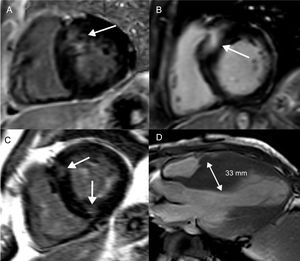

La miocardiopatía hipertrófica es una miocardiopatía genética, identificada por un aumento inexplicable del grosor de la pared del VI con una cámara no dilatada55. Se han descrito más de 1.400 mutaciones, que se acompañan de varios fenotipos55. El engrosamiento de la pared del VI es más habitual en el septo basal del VI, pero también tiene lugar en patrones apicales y medioventriculares (figura 3D). Un engrosamiento de la pared del VI ≥ 30 mm en cualquier segmento es un factor de riesgo de MSC (figura 3D)56. La formación de aneurisma apical se asocia con obstrucción medioventricular, probablemente a causa de la exposición crónica del ápice del VI a la elevada tensión parietal causada por el aumento de la presión sistólica57,58. Esto origina isquemia y fibrosis de sustitución focal del ápice del VI58. La obstrucción medioventricular con un gradiente ≥ 30 mmHg (HR=3,19; IC95%, 1,62-6,29; p <0,001), con o sin formación de aneurisma apical, fue un determinante independiente de AV y MSC en un estudio llevado a cabo en 490 pacientes japoneses58. Varios estudios han proporcionado pruebas sobre la asociación del RTG con las AV y la MSC (tabla 3)59-73. No solo la presencia, sino también la extensión del RTG, se relaciona con el riesgo de AV/MSC (figuras 3A y B)59,61,62,66,67,70,71. Además, el patrón del RTG tiene implicaciones pronósticas: aunque la presencia de RTG en los puntos de inserción del ventrículo derecho es característica del diagnóstico de MCH, no parece que pronostique un mayor riesgo de MSC (figura 3C)74.

Fibrosis focal en la miocardiopatía hipertrófica. Cortes del ventrículo izquierdo de eje corto (A-C) y un corte apical de eje largo (D) que muestran distintos patrones de RTG y engrosamiento de la pared del VI en la miocardiopatía hipertrófica. A: engrosamiento basal y septal del VI y colocalización del RTG. B: localización basal y septal más extensa del RTG, lo que representa un mayor riesgo de MSC. C: RTG en las uniones anterior e inferior derechas del VI, lo que no se relaciona con un aumento del riesgo de MSC. D: patrón medioventricular de engrosamiento del VI, con un septo interventricular de 33 mm; tanto la hipertrofia medioventricular como el engrosamiento del VI ≥ 30 mm son marcadores del riesgo de MSC. MSC: muerte súbita cardiaca; RTG: realce tardío de gadolinio; VI: ventrículo izquierdo.